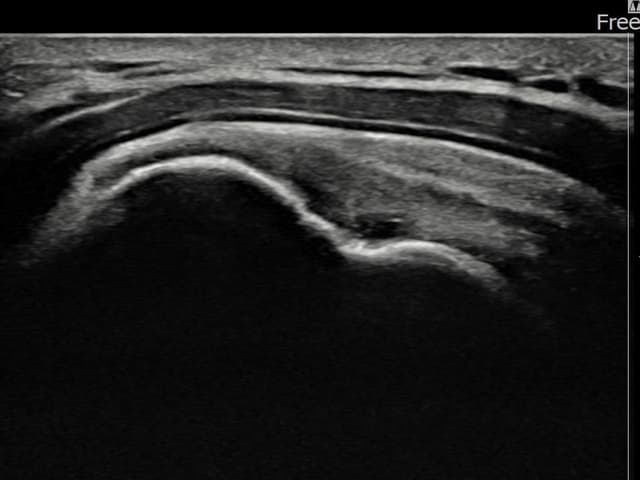

左侧 冈上肌腱 石灰化肌腱炎

16mm × 11mm